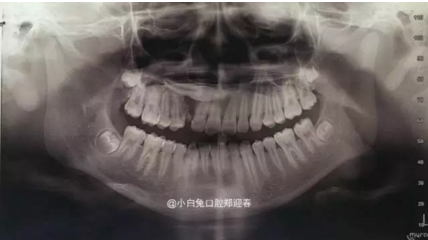

最近朋友圈轉(zhuǎn)發(fā)最多的一張片子,你知道嗎?

1.png